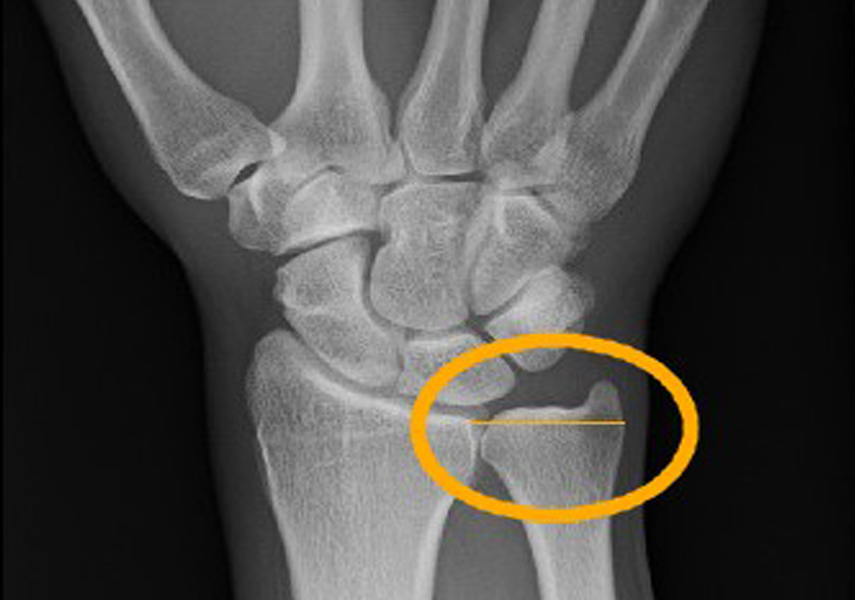

手関節の尺側には三角線維軟骨複合体とよばれる、軟骨と靭帯などで手根骨と尺骨を結合して安定化させるクッションの役割を担う組織があります。日本名が難しいのでTFCCと呼ばれることが多い部位になります。

これはグリップ動作を伴うテニスや野球などのスポーツにおいては高頻度で発症する障害です。手関節の尺側に対して頻回に圧縮や牽引、剪断力が加わることによって生じる慢性外傷が多いとされ、ラケットスポーツなどにおいては未熟なグリップ動作がこの損傷を招くことになるとも報告されています。また、手関節の捻挫の後などに3週間~4週間経って捻挫が治る時期になっても手関節の尺側部に痛みが残り、手関節を動かすと痛みが走る場合、しばしばこの損傷が原因になっていることがあります。この部位はレントゲン検査では異常を認めないため、痛みと圧痛部位と発症前後のケガなどから判断していきますが、場合によっては手関節を内視鏡検査して調べていくことになります。

TFCCの構成要素としては、三角線維軟骨、尺側側副靭帯、掌背側の遠位橈尺関節靭帯、関節円板類似体、尺側手根伸筋腱の腱鞘で構成されます。TFCCの主な機能を考えていくと、一番大きな働きとしてあげられるのが遠位橈尺関節の安定性の維持になります。遠位橈尺関節の運動は、単純な回旋運動だけでなく並進運動の成分も含まれ、これをTFCC、骨間膜、方形回内筋で維持していると考えられています。また、橈骨手根関節の尺側側の支持機構としても働き、尺側手根伸筋腱の腱鞘は手根骨と尺骨を結ぶ強靭な繊維となり、手関節の安定性に寄与しています。